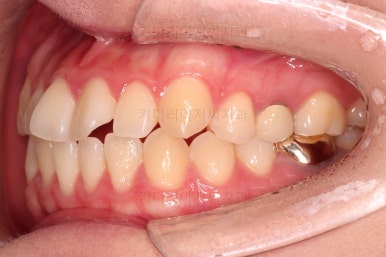

1. 처음 내원 시의 입안의 모습

부산치아교정잘하는곳 키다리아저씨치과에 처음 내원하셨을 당시의 입안 모습입니다.

얼핏 보면 많이 삐뚤어지지는 않은 편인데, 눈에 바로 띄는 앞니가 뻗쳐 있으면서 획 돌아있는데요. 정렬이 필요한 상황이었습니다.

어금니쪽은 많이 삐뚠 편은 아니었으며, 윗니 앞니가 많이 앞으로 뻗쳐 있는 상태였습니다.